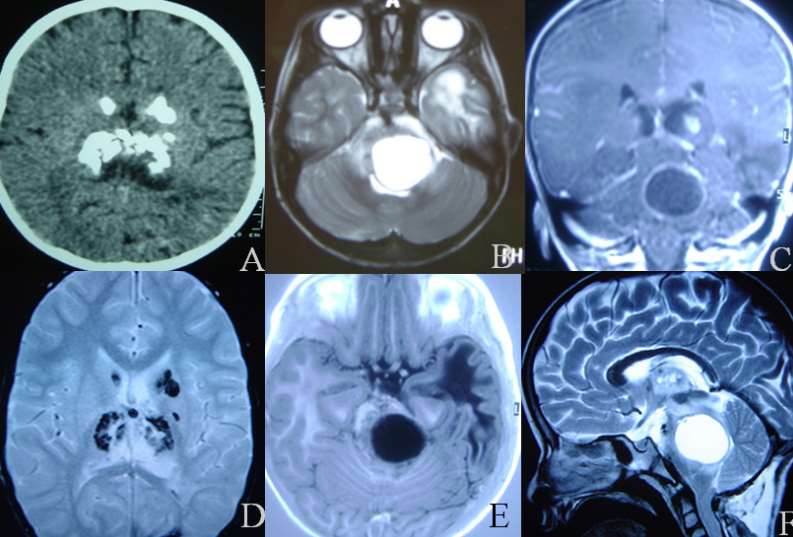

Mesmo que as calcificações dos núcleos da base tenham sido descritas há muito tempo atrás, a associação com leucoencefalopatia, calcificações cerebrais e cistos (LCC) é uma entidade muito rara descrita em 1996.5 Nós apresentamos um caso novo de LCC e discutimos os achados clínicos, neurorradiológicos e histopatológicos relacionados a essa entidade.